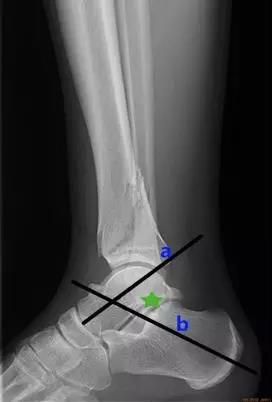

踝关节

- 结节关节角:是在跟骨后关节面最高点与跟骨结节间做一连线,再在跟骨前端背侧最高点与后关节面最高点做另一连线,连线相交成角,称为结节关节(Böhler角)。

- 正常值:25°~40°

- 临床意义:跟骨结节关节角减小,提示跟骨骨折或扁平足;跟骨结节关节角增大,提示弓形足。

- Gissane角:从跟骰关节面连线与后关节面后缘连线 的夹角。

- 正常值为:120°~145°。

- 临床意义:跟骨骨折时角度可能会发生变化,该角度提示前中后关节的关系。